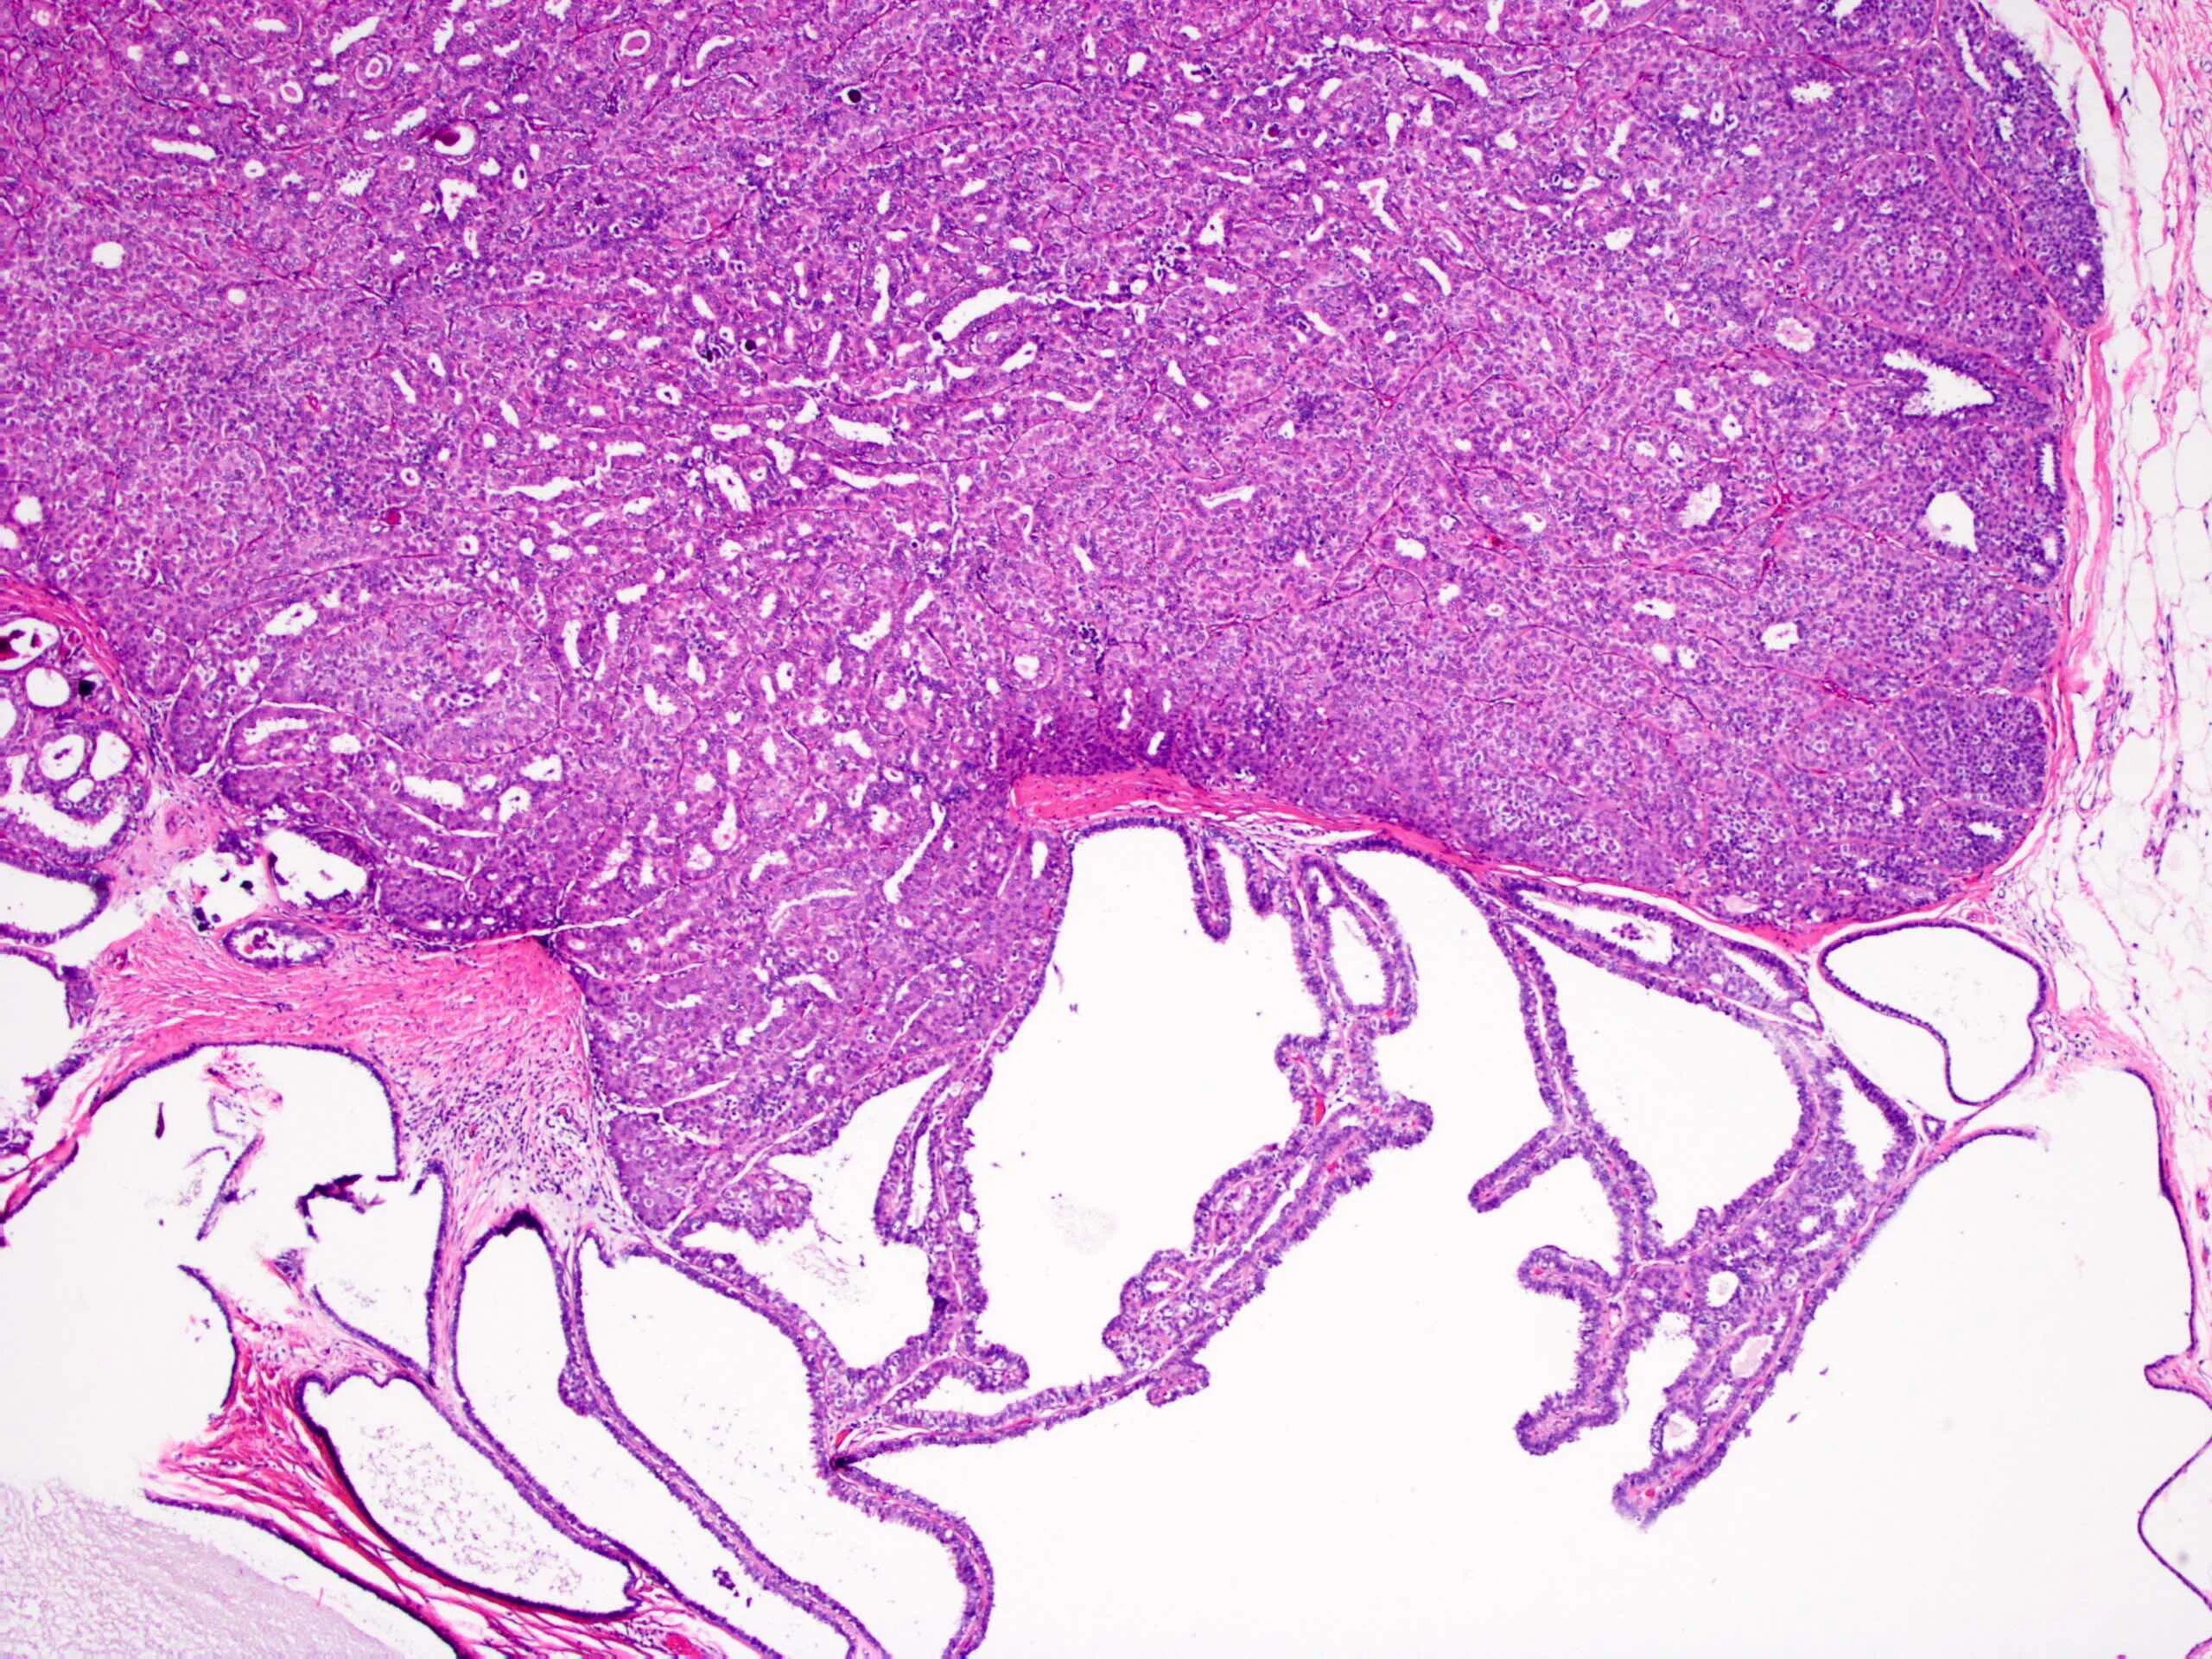

Папиллома гистология